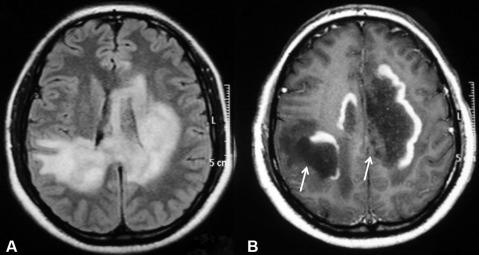

The clinically isolated syndrome (CIS) refers to the first clinical episode of neurologic symptoms suggestive of multiple sclerosis (MS), such as vision problems, muscle weakness, or sensory symptoms. It indicates an early or relapsing stage of multiple sclerosis. The symptoms are typically caused by a single lesion or plaque in the central nervous system found through magnetic resonance...